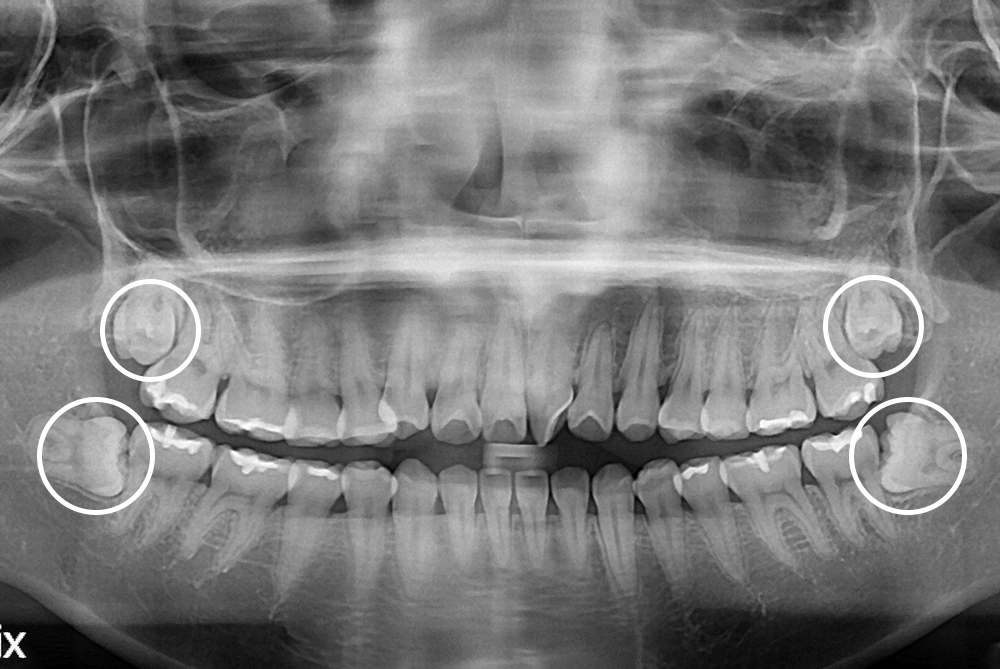

[사랑니] 매복 사랑니 발치

치료후 : 2018-10-10

세종치과는 구강악안면외과학 박사이신 원장님이 발치하는 치과입니다.